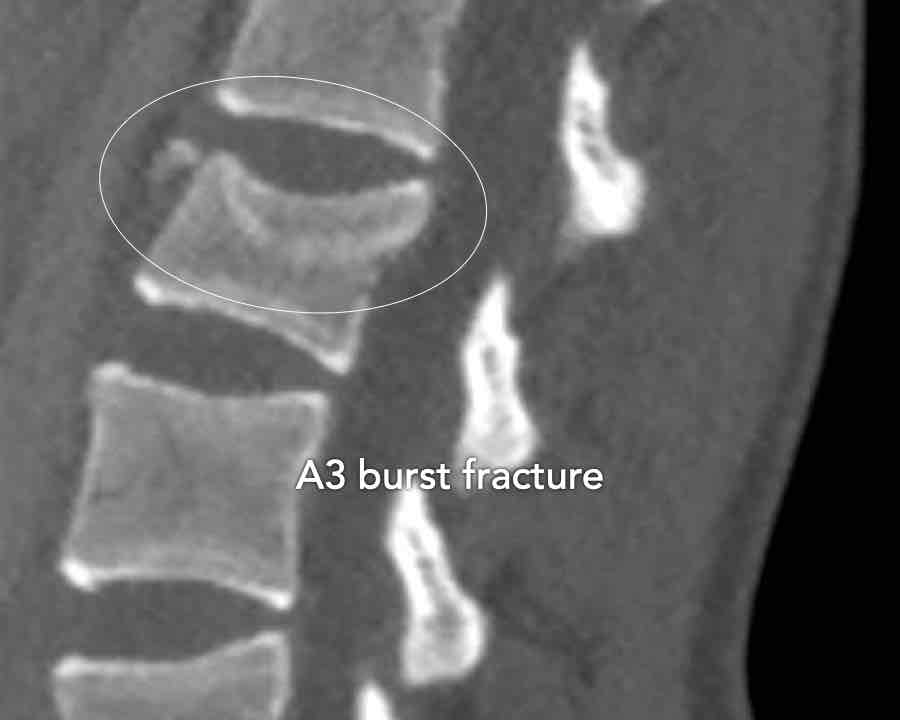

A3 Incomplete Burst fractures

Fracture with any involvement of the posterior wall; only a single endplate fractured.

A vertical fracture of the lamina is usually present and does not constitute a tension band failure.

What is the AO-type of the vertebral body fracture based on only these two inages?

Findings:

- Fractures of the vertebral body with involvement of upper endplates (1 points) and posterior wall (2 points)

- Bulging of the posterior wall without any other signs of dislocation is the result of the burst fracture.

Therefore no C injury.

Conclusion

Injury type A3